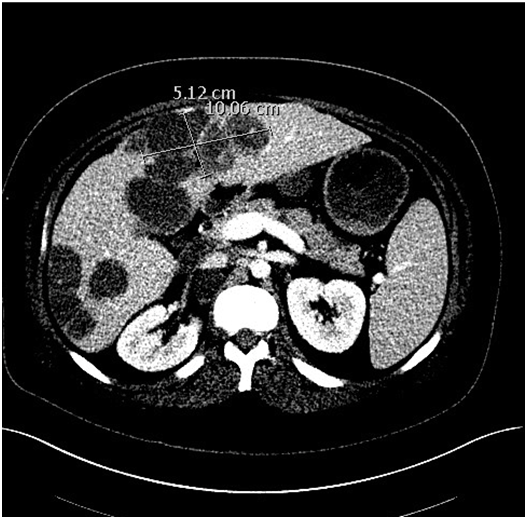

The patient is a 20-year-old male who initially noticed swelling in his scrotum for approximately 3-4 months after being hit with a pellet gun in his groin. He was evaluated by a local physician and treated for epididymitis, but after no improvement in symptoms, he presented to the Emergency Department at an outside hospital with worsening scrotal and abdominal pain. A CT abdomen/pelvis was performed and revealed wide-spread metastatic disease to the liver, lungs, and retroperitoneum (Figure 1A) (Figure 1B). He underwent a testicular ultrasound (U/S), which revealed an enlarged right testicular mass. He subsequently underwent a right-sided orchiectomy and was diagnosed with nonseminomatous testicular cancer (further specifics of pathology were pending at time of initial management). The patient was then discharged home to follow up as an outpatient.

Figure 1 (CT without contrast prior to therapy).